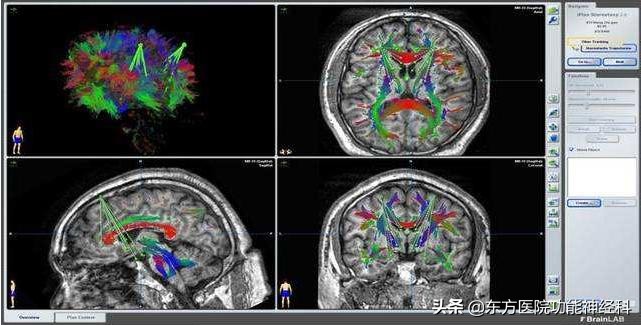

手术治疗精神疾病已有130多年历史,目前手术治疗精神病的技术已十分成熟,其手术靶点经过了几十年的探索和总结,随着神经生物学、神经解剖学、神经电生理学的进步,神经核团调控技术也逐渐成熟。神经核团靶点定位即有解剖学定位,又有电生理定位,双定位模式保障了定位的精准性。特别是现阶段使用的第五代脑立体定位技术,即CT/MRI/DTI图像融合下的可视化、实时、个体化的数字精确定位,其定位误差从过去盲式定位误差的10mm~13mm,发展到现在的数字定位误差±0.5mm。同济大学附属东方医院(南院)功能神经科的“第五代脑立体定向技术”原理是利用CT/MRI/DTI图像融合建立三维坐标准确定位靶点位置(图1),就好像发射导弹一样,先要找到发射目标的位置;它能够更加精准的对靶点进行精确的调控。很多家属担忧或疑虑手术后会出现并发症,例如,担心术后患者出现呆傻、偏瘫、失语等。其实,这类手术属于微创手术,手术可通过手术机器人完成(图2),手术切口微小,进入脑内的治疗电极仅仅2~3毫米粗细,并且也不在脑的智能区、运动区和语言区域手术,因此,上述并发症理论上完全不可能发生。

图1:利用CT/MRI/DTI图像融合建立三维坐标准确定位靶点位置